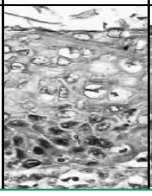

this is?

mild dysplasia, CIN 1